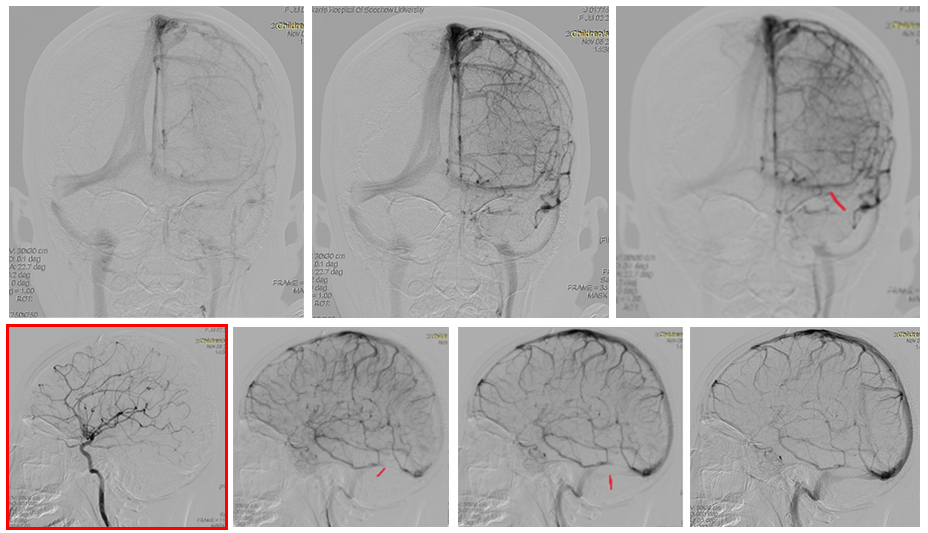

头痛由颅内压升高引起,通过腰椎穿刺和眼底检查(乳头水肿)证实。可能继发于内分泌异常、感染、维生素摄入、生长激素使用、皮质类固醇戒断、重金属中毒、脑静脉血栓等因素。MRI血管成像显示乙状窦狭窄可能是当前唯一可识别的原因。

首选药物治疗并持续监测颅内压和视力。50%病例通过长期药物治疗可解决问题,疗程需持续至症状缓解后数月(通常约8个月)。药物治疗失败时可考虑脑室-腹腔分流术,或乙状窦狭窄支架植入术。